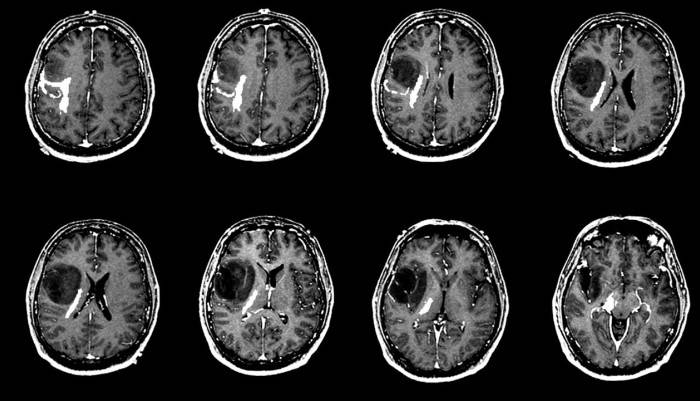

Beyin tümörleri hakkında merak ettikleriniz...